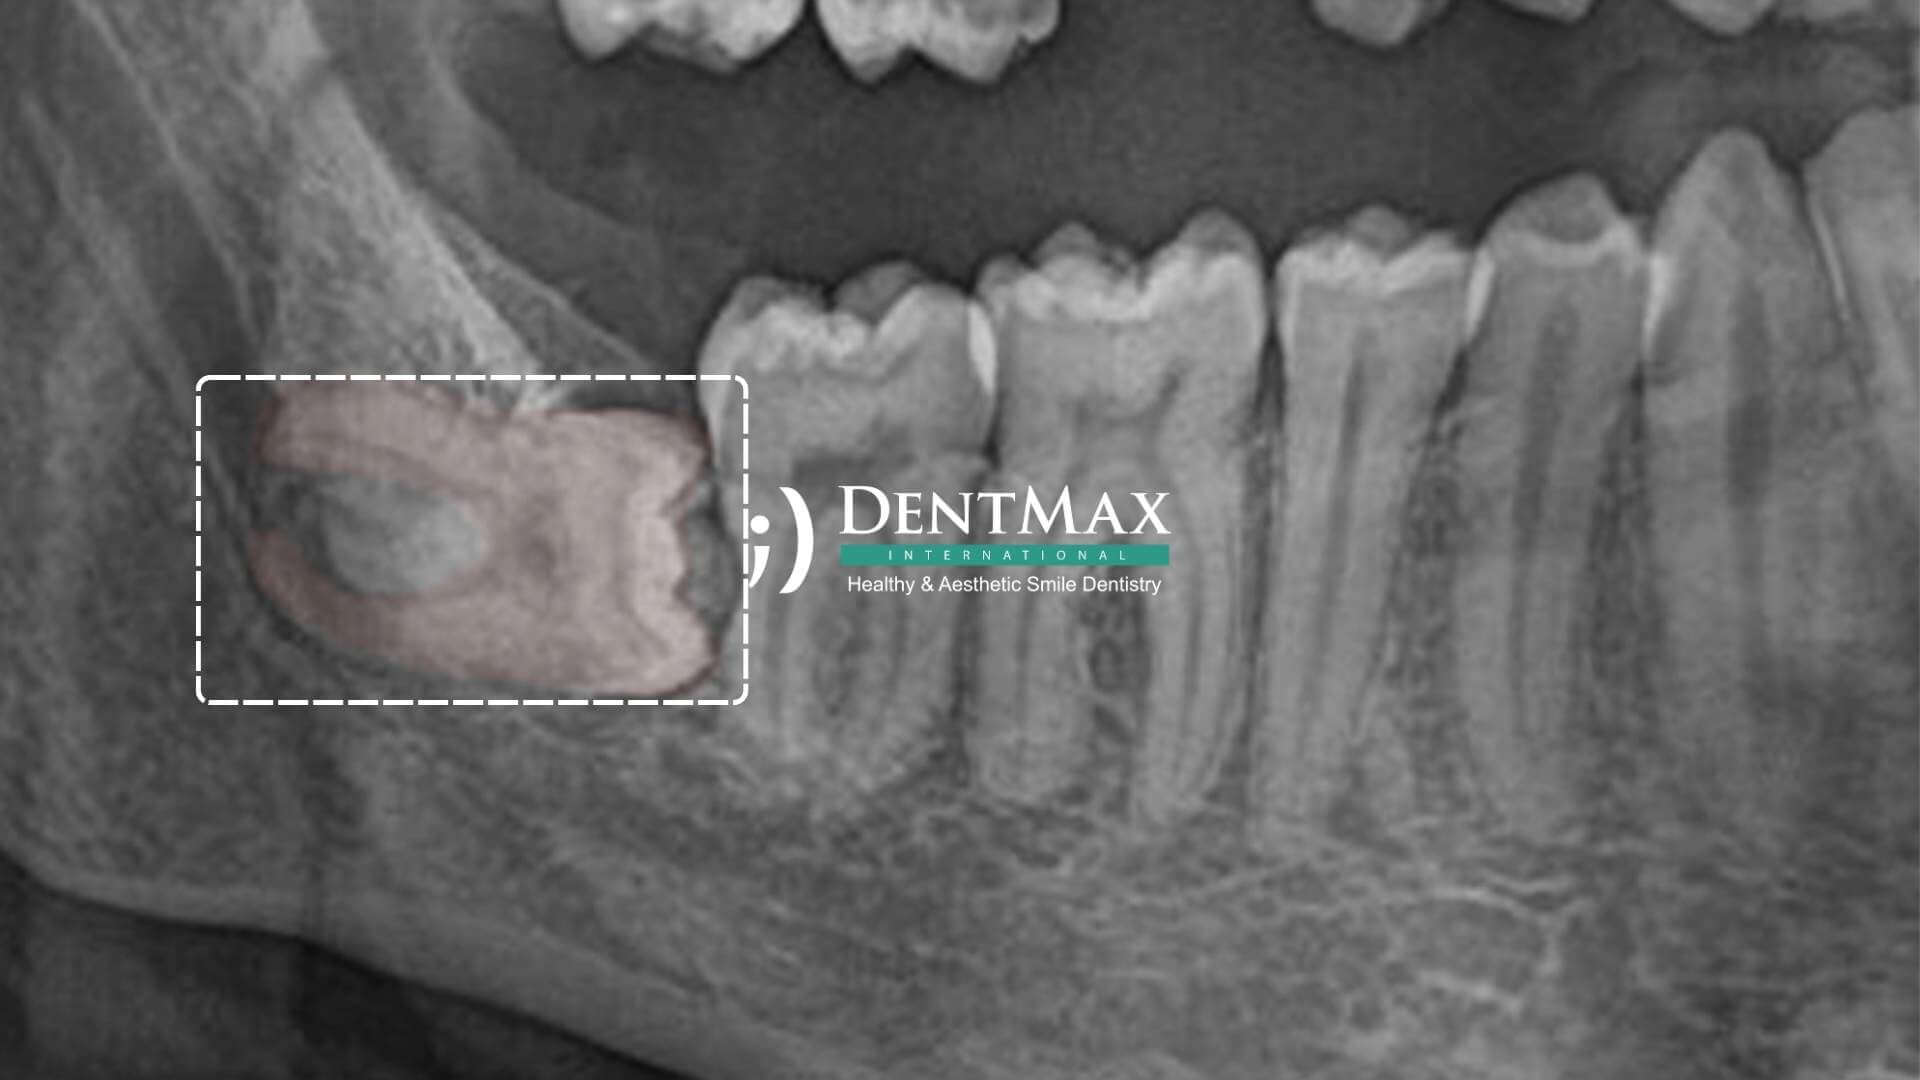

Tomografi ve Tecrübeli Hekim Neden Önemli?

20 yaş dişleri sinir kanallarına veya sinüs boşluklarına çok yakın olabilir.

Tomografi yapılmazsa sinir zedelenmesi, dudakta hissizlik, sinüs zedelenmesi, komşu dişlerde kırık gibi komplikasyon riski artar.

Panoramik röntgen veya dental tomografi ile analiz